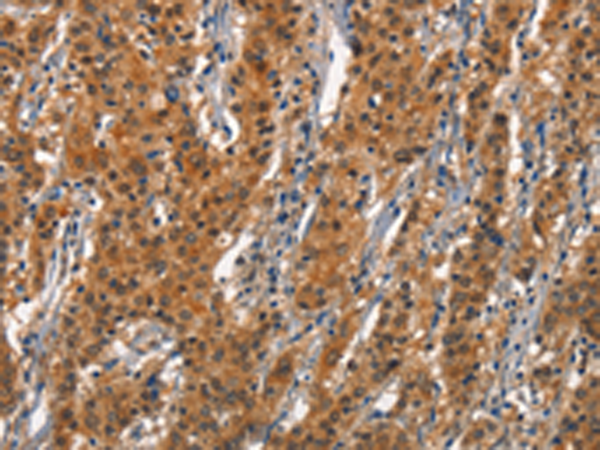

分类: 科研抗体货号: P04303别名: BMP9; HHT5; BMP-9应用: WB,IHC反应种属: Human, Mouse